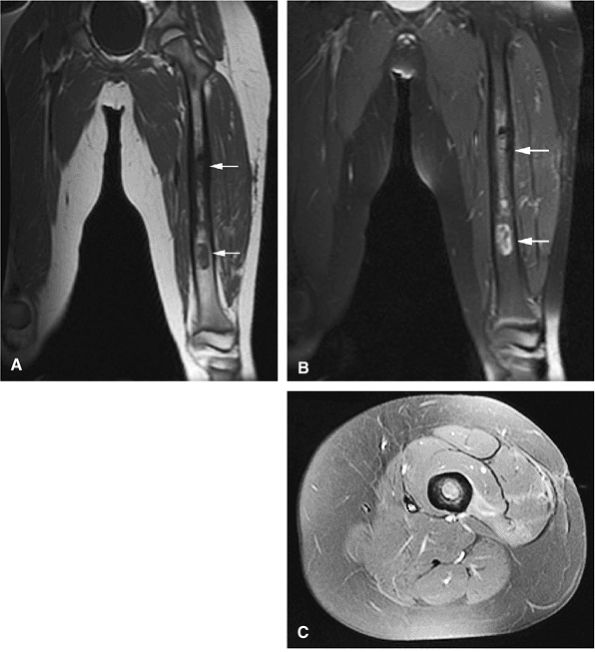

Skip lesions and multiple sites of involvement are common in multicentric osteosarcoma, which affects a younger age group.107

FIGURE 14-71 ● (A) Anteroposterior radiograph showing blastic osteosarcoma as a sclerotic metaphyseal focus with aggressive periosteal reaction (arrows). (B) On a T1-weighted axial image, the lesion is seen as a low-signal-intensity area of marrow replacement with associated soft-tissue extension (arrows). On coronal (C) and axial (D) fat-suppressed T2-weighted fast spin-echo images, hyperintense tumor and soft-tissue component are demonstrated. Soft-tissue component is hyperintense on sagittal fat-suppressed T2-weighted fast spin-echo image (E) (arrows).

FIGURE 14-72 ● Osteosarcoma of the distal femur. (A) Coronal T1-weighted image demonstrates marrow infiltration (arrowhead) with cortical destruction and extension into the adjacent soft tissues (arrows). (B) On a sagittal proton density-weighted image, aggressive periosteal reaction and soft-tissue extension are demonstrated (arrows). (C) On a coronal fat-suppressed T2-weighted fast spin-echo image, the tumor is hyperintense (black arrows) with hypointense areas corresponding to sclerosis (white arrow). Aggressive periosteal reaction is hyperintense (arrowhead). (D) Coronal contrast-enhanced fat-suppressed T1-weighted image shows central nonenhancing areas, consistent with necrosis (arrows).